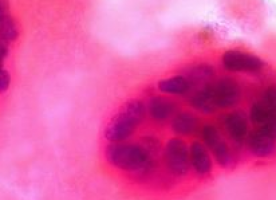

To determine the role of TFF3 in breast cancer, researchers measured its level in tissue samples from normal breasts, benign breast lesions, in situ carcinomas, invasive carcinomas, and involved lymph nodes. TFF3 was expressed in the majority of benign and malignant breast lesions studied. Well-differentiated tumour types expressed higher levels of TFF3.

There was a positive association between TFF3 protein expression and microvessel density, suggesting that it stimulates angiogenesis in breast tumours.

TFF3 was expressed at higher levels in primary tumours with associated metastasis, and its expression was higher in malignant cells that have metastasised away from those within the primary tumour. There appears to be a switch in the normal polarised secretion of TFF3 in invasive cancer, which allows it to exert invasion-promoting effects.